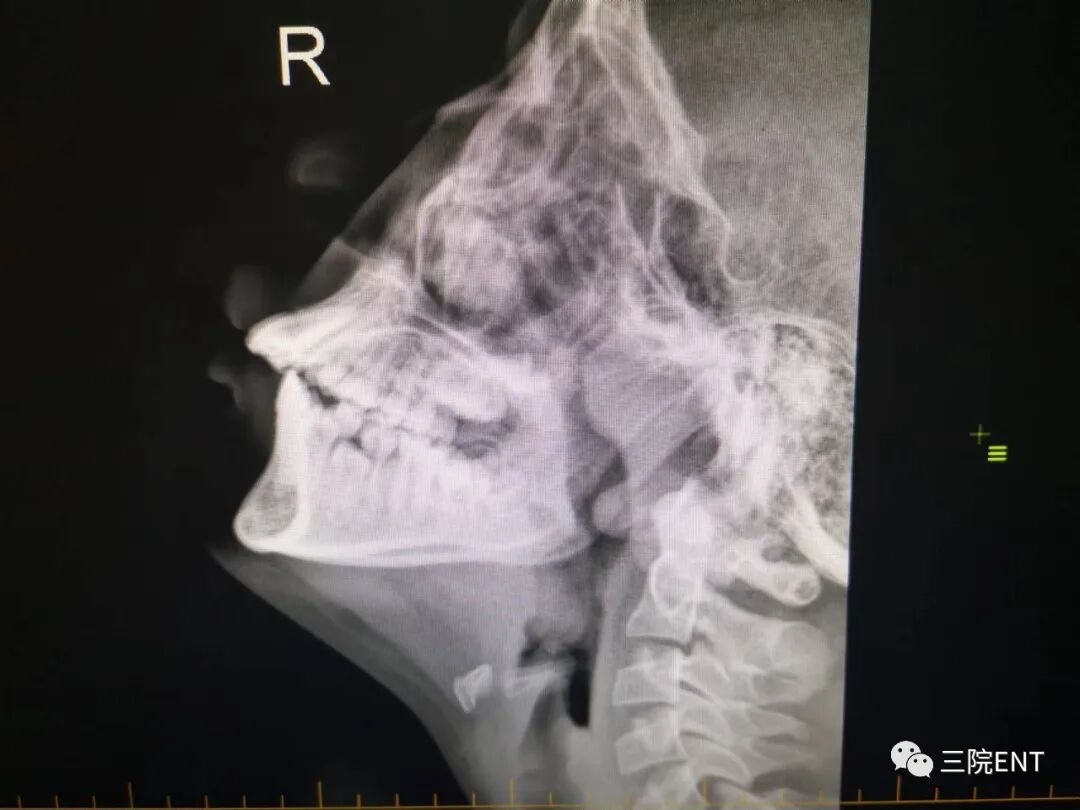

4.鼻内镜检查鼻咽顶后壁可见粉红色软组织团块;鼻咽X线侧位拍片或CT扫描为决定性诊断

图片图片